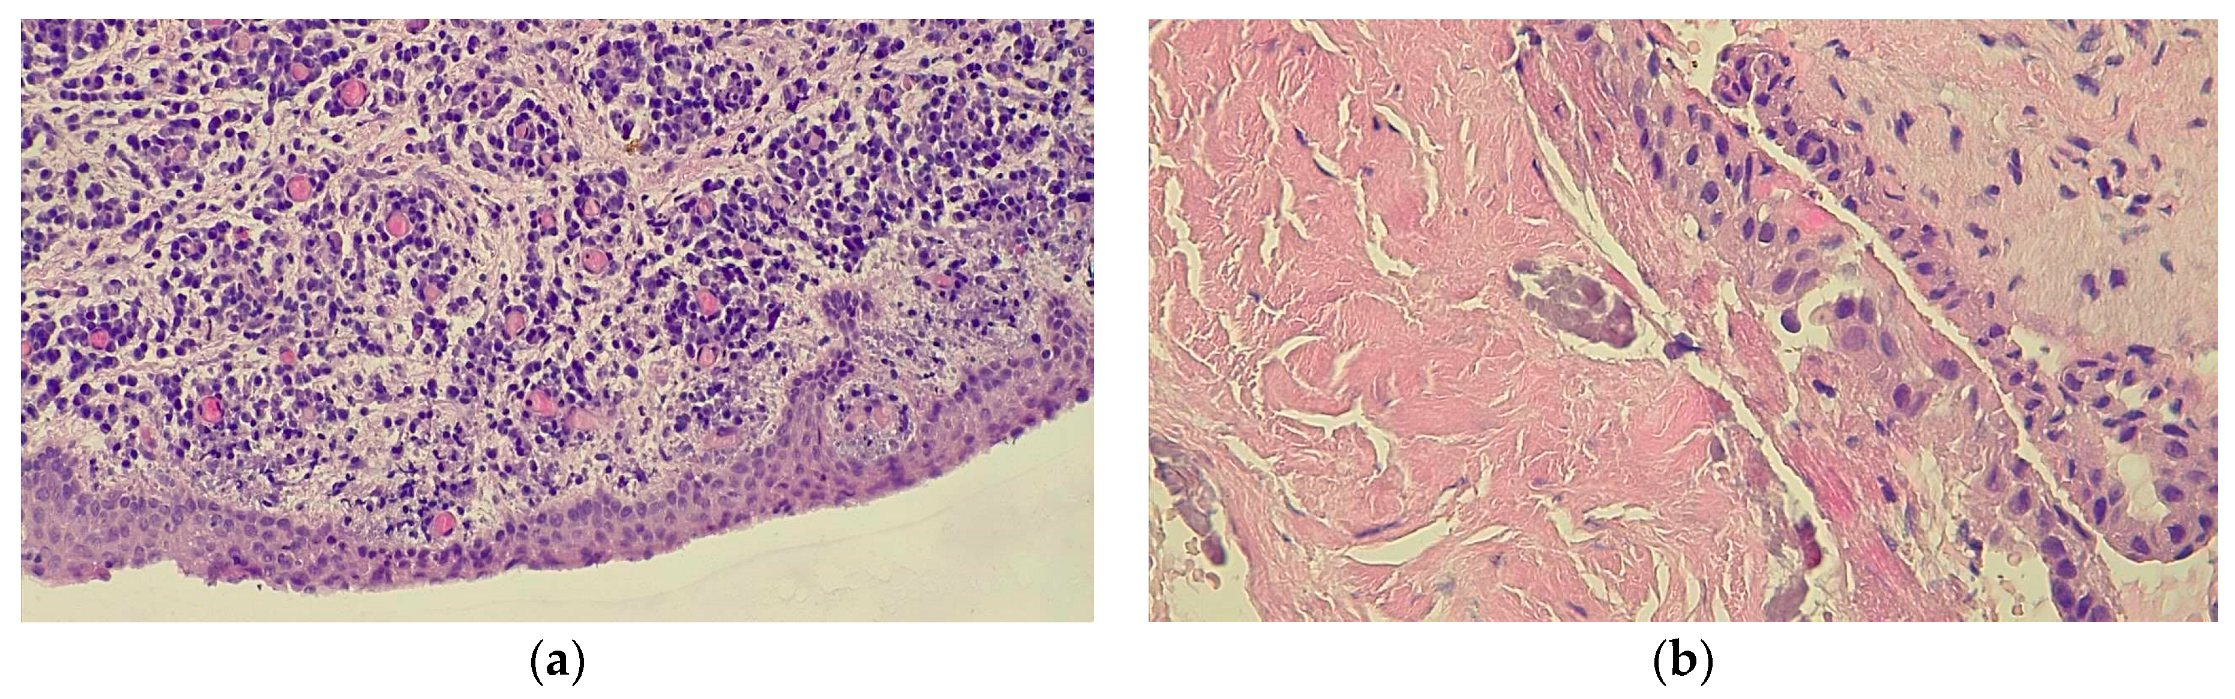

- Parul, B.; Purv, P. Recurrent dentigerous cyst with malignant transformation of cyst lining–a case report. J. Pierre Fauchard Acad. (India Sect.) 2012, 26, 59–63. [Google Scholar] [CrossRef]

- Borghesi, A.; Nardi, C.; Giannitto, C.; Tironi, A.; Maroldi, R.; Di Bartolomeo, F.; Preda, L. Odontogenic keratocyst: Imaging features of a benign lesion with an aggressive behaviour. Insights Into Imaging 2018, 9, 883–897. [Google Scholar] [CrossRef] [PubMed]

- Spoorthi, B.R.; Rao, R.S.; Rajashekaraiah, P.B.; Patil, S.; Venktesaiah, S.S.; Purushothama, P. Predominantly cystic central mucoepidermoid carcinoma developing from a previously diagnosed dentigerous cyst: Case report and review of the literature. Clin. Pract. 2013, 3, e19. [Google Scholar] [CrossRef] [PubMed]